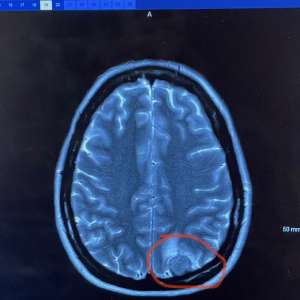

Also images of Jess's scans.